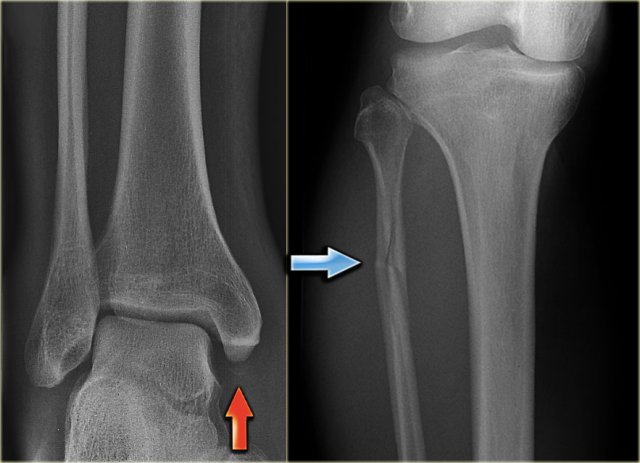

This patient had a twisted ankle and the only abnormality is seen on the lateral view.

This was thought to be an avulsion of the posterior malleolus.

Knowing that this can be the only clue to a high Weber C, additional radiographs were taken.

Continue with the images of the lower leg.

A subtle high fibula fracture is seen (arrow).

Final diagnosis is a Weber C fracture or according to Lauge Hansen: Pronation Exorotation injury stage 4.